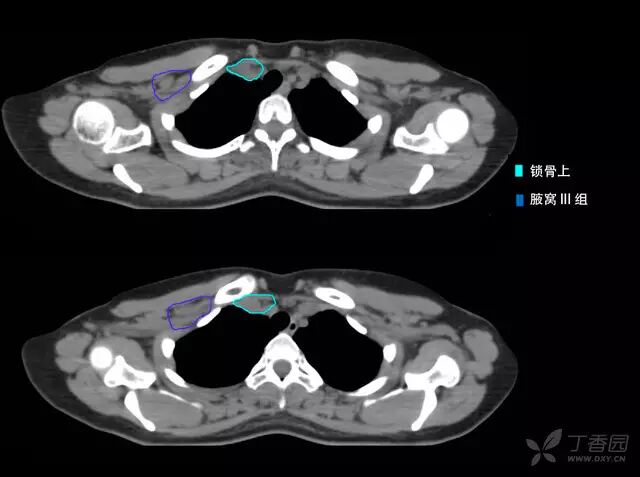

病例 1:左侧乳腺癌术后 t3n3(11/5)m0 iiib 期(下图仅显示锁骨上 ctv